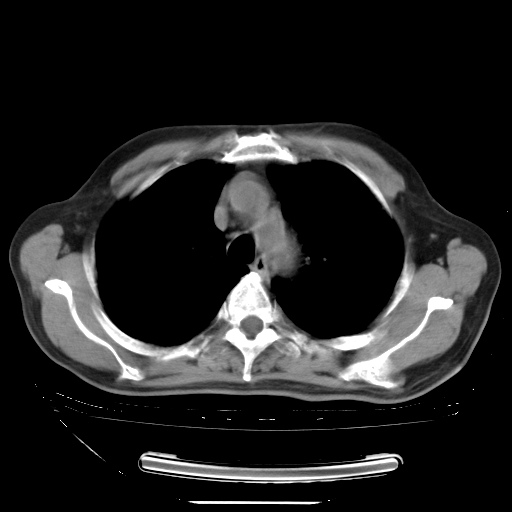

今天复查肺部CT,发现双肺广泛磨玻璃样改变。所以我把3月19日和5月9日相隔50天的肺部CT上传。请大家会诊。

2009年3月19日肺部CT片。

5月9日肺部CT(在4月27日齐鲁医院肺部CT描述部分肺组织磨玻璃样改变,12天后肺组织广泛磨玻璃样改变)